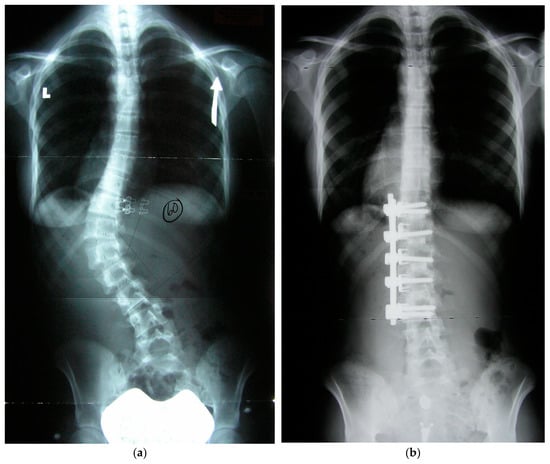

Figure 1.

Preoperative coronal and sagittal radiographs (a,c) and postoperative radiographs (b,d). (a) AIS Type 5 preoperative coronal (upright indicated by arrow) radiograph with 60 degrees scoliosis. (b) Postoperative radiograph at one year after traditional convex technique.

Preoperative and postoperative coronal radiographs (a,b).